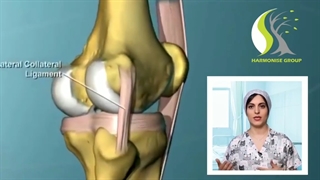

پارگی مینیسک یکی از آسیب‌های شایع است که بر مفصل زانو اثر می‌گذارد. مینیسک‌ها دیسک‌های C شکلی هستند که از جنس غضروف محکمی به نام فیبروکارتیلاژ می‌باشند. مینیسیک‌ها بین استخوان ران و استخوان ساق پا قرار گرفته و برای توزیع بار و جذب شوک در مفصل زانو بسیار مهم هستند.